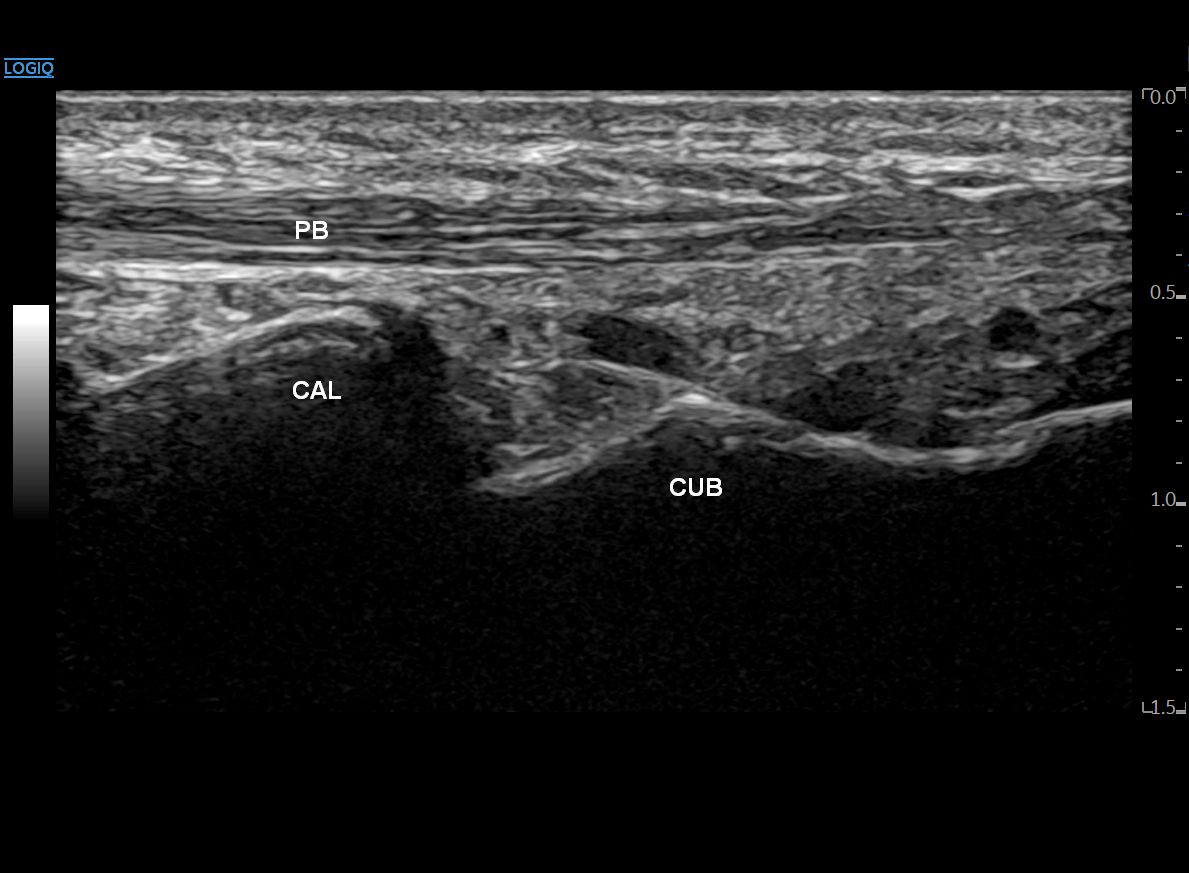

좌측 모식도 @ DOI: 10.1002/sono.12300 / 우측 초음파 영상은 직접 스캔했습니다

민트색 박스로 표시한 부위에

프로브를 댄 영상입니다.

종골(CAL)과 입방골(CUB)이 만나는

종입방 관절이 보이고요.

그 위로 제5중족골을 향해 달려가는

단비골근건(PB)이 보입니다.